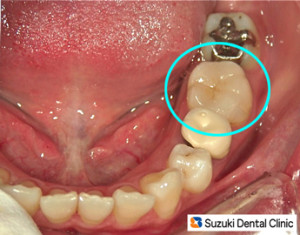

100%セラミック詰め物

コラム「100%セラミック詰め物」の画像